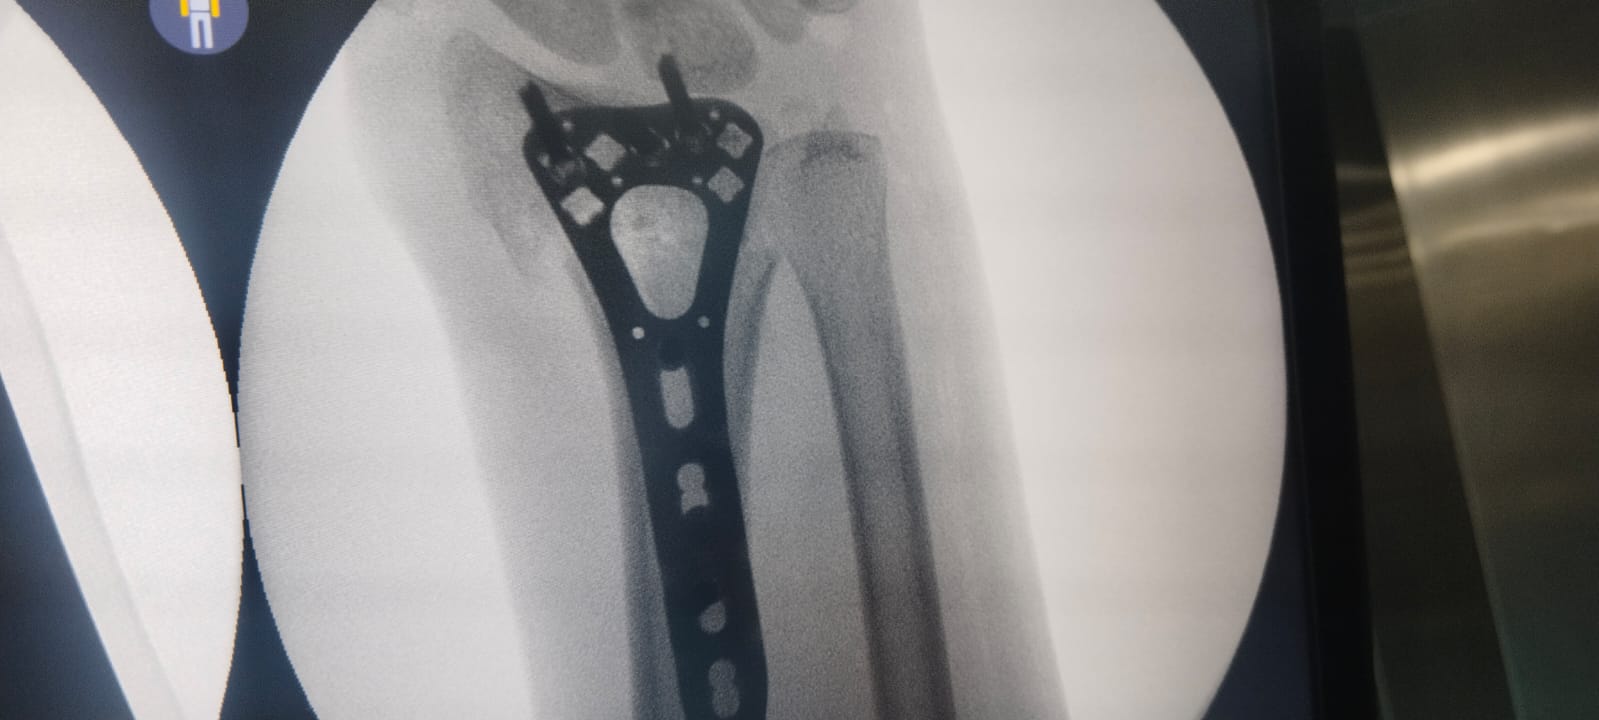

Pre-Operative X-ray

• Displaced distal radius fracture

• Loss of normal anatomical alignment

• No joint surface involvement

Post-Operative X-ray Findings

• Anatomical reduction achieved

• Correct placement of plate and screws

• Strong and stable fixation